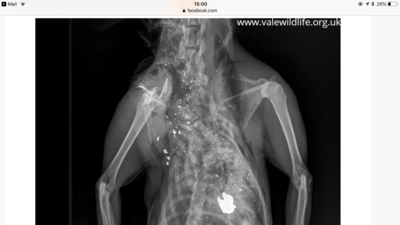

The Post- Mortem indicated he had been shot with exploding bullets, which did not kill him, his neck was stamped on causing his bones to shatter and his shoulder to break, as he lay dead or dying the underside of his throat was gnawed at by a dog or dogs and his tail was cut off.